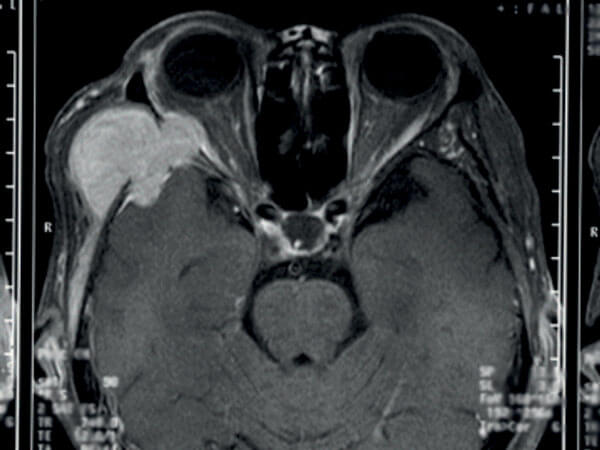

Figure 1: Brain MRI scan showing a lateral sphenoid wing meningioma invading the orbit.

Meningiomas comprise 25% of intracranial tumours and are most commonly located in order of frequency along the convexity, parafalcine area, sphenoid ridge, tuberculum sellae and olfactory groove. Sphenoid tumours are the commonest encounter in the eye clinic because of the sphenoid bone forming the lateral orbital wall and its close relation to the visual pathway and ocularmotor nerves. Sphenoid ridge tumours are divided into those arising from the outer, middle and inner thirds; outer and middle ones are relatively silent unless they erode the greater wing and invade the orbit as seen in Figure 1. Inner third tumours are in close proximity to the superior orbital fissure and optic canal thus can present with nerve palsies or a compressive optic neuropathy.